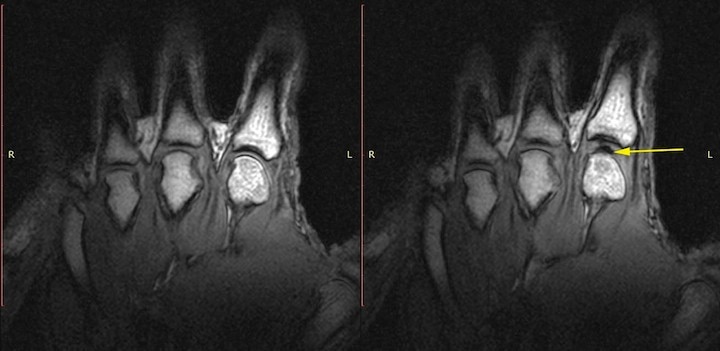

しかし、2015年、カナダのアルバータ大学の研究プロジェクトは、被験者の中手骨節関節をMRIで撮影し、クラッキング音が鳴るまでのプロセスを観察したところ、クラッキング音が鳴った後も気泡が滑液に残っていたことから、「クラッキング音は、気泡が弾けるときではなく、気泡が形成されるときに発生する」と主張し、従来の「キャビテーション理論」と矛盾する新たな理論として、近年、議論を呼んでいる。